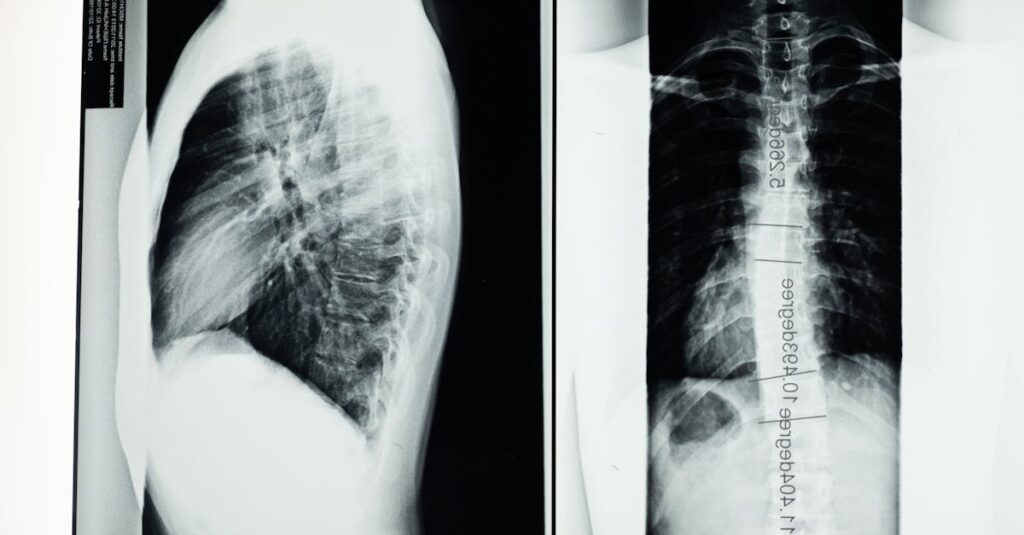

La sténose spinale est une condition qui se caractérise par un rétrécissement du canal rachidien. Cela crée une pression sur la moelle épinière et les racines nerveuses, entraînant douleur et inconfort. Cet article présente les options de traitement disponibles pour cette pathologie, allant des méthodes conservatrices aux interventions chirurgicales.

La sténose spinale résulte souvent d’une usure liée à l’âge, mais peut également être causée par des blessures ou des maladies. Ce rétrécissement peut se produire à divers niveaux de la colonne vertébrale, y compris dans les zones cervicales et lombaires. Les symptômes varient en fonction de la localisation, mais incluent généralement des douleurs, des engourdissements ou une faiblesse dans les membres.

La sténose spinale est une condition caractérisée par un rétrécissement du canal vertébral, ce qui peut entraîner une pression sur la moelle épinière et les racines nerveuses. Cette condition peut provoquer des douleurs, de la faiblesse et une altération de la fonction nerveuse. Dans de nombreux cas, les patients recherchent des options de traitement pour soulager leurs symptômes et améliorer leur qualité de vie. Il existe plusieurs stratégies, allant de méthodes conservatrices à des interventions chirurgicales.